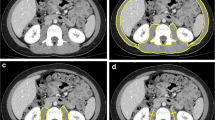

The method is based on X-ray attenuation measured by a computer program that reconstructs cross-sectional images represented by a 2-D map of pixels [8]. The pixels are given a numerical value (Hounsfield unit, HU), based on tissue attenuation (related to electron density) that are colored white [most dense (i.e., water)] and black [least dense (i.e., air)]. Bone, skeletal muscle, and adipose tissue, as well as visceral organs, have specific HU ranges, allowing for their identification in the cross-sectional images [11, 12]. The tissue area (cm2) of the cross-sectional image is subsequently calculated by multiplying the number of pixels for a given tissue by its surface area.

For the study of muscle, CT scanning is usually performed at 130-kVp exposure [13]; exposure and scanning times are 0.1 and 0.4 s, respectively. Slice thickness is comprised between 6 and 10 mm. After the identification of the appropriate HU for non-bone non-adipose tissue (primarily skeletal muscle and skin), the entire area with these HUs is measured for each slice. Subsequently, the skin is eliminated from the image to assess the amount of skeletal muscle in each CT image. To more easily “erase” skin (which has the same HU as skeletal muscle), specific software programs are available to automatically remove the outer two-voxel layers (1.835–2.62 mm) of the air–tissue interface.

Due to its high-resolution, CT allows muscle quantity to be measured accurately. CT also provides valuable information on muscle quality by evaluating muscle density, a parameter related to intra- and extramyocellular lipid deposition. The degree of muscle attenuation, in turn, has been associated with muscle strength and adverse health outcomes independent of muscle cross-sectional area [14, 15]. Similar to MRI, the widespread implementation of CT in the field of sarcopenia is hampered by the high cost of equipment, space requirement and need of highly qualified personnel. Although the time necessary for image acquisition is shorter than with MRI, it should be considered that CT involves radiation exposure (up to 30 mrem per scan) [16]. Similar to MRI, the field of application of CT in the context of sarcopenia is currently limited to small-scale research studies.